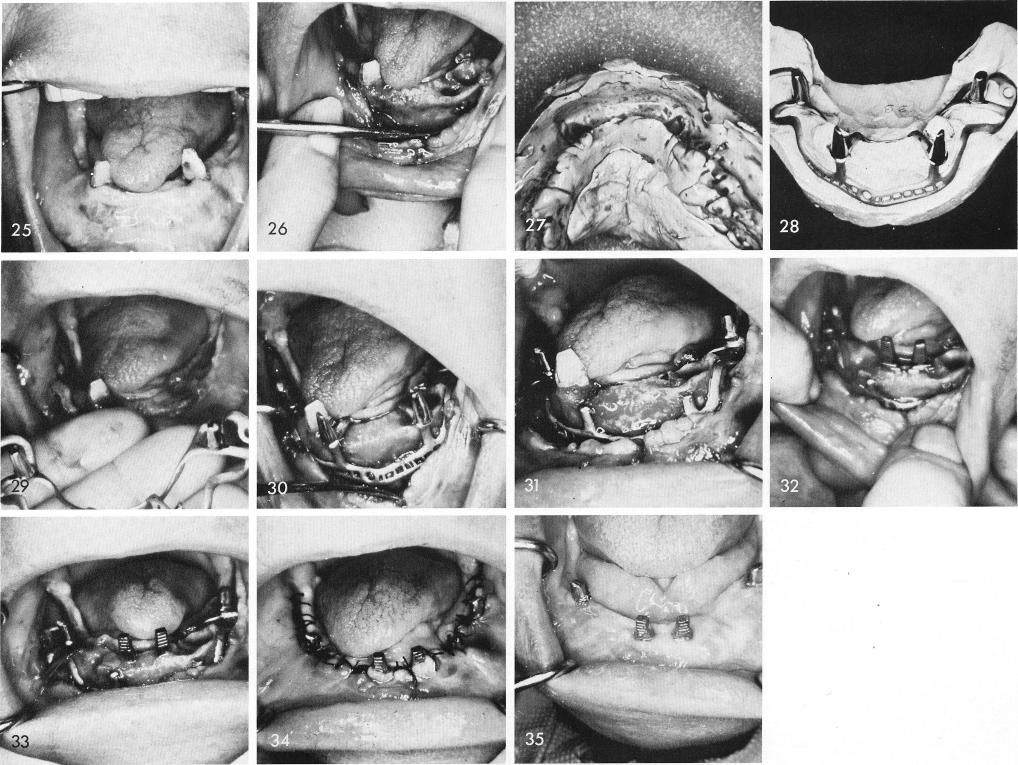

In this situation, the patient had only two remaining teeth, fig. 25, of which one was later removed. She also had a severe overbite and overjet which I thought could be greatly reduced by designing the anterior posts of a universal subperiosteal implant to rest extremely in a labial position. The tissues were incised and retracted as well as the left loose cuspid extracted and an impression for the universal type subperiosteal implant was taken, figs. 26, 27. Fig. 28 shows the anterior posts on the labial edge of the ridge, which when inserted over the bone, figs. 29, 30, made it impossible to suture the tissues closed. By removing both anterior posts and their secondary supporting struts, still leaving the entire implant in one piece, thus not reducing its over-all retention, fig. 31, a double-posted bladevent was inserted in the anterior quadrant, figs. 32, 33, and the tissues were sutured together, fig. 34. Healing was excellent, fig. 35. The x-ray shows

1 Case showing a patient with severe overbite and overjet